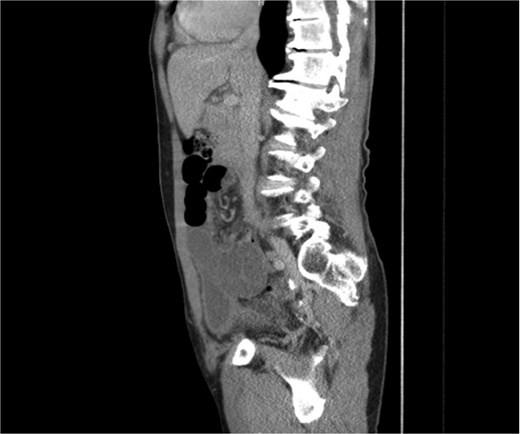

We present a case of a 76-year-old gentleman who had a previous elective laparoscopic TAPP right inguinal hernia repair in another hospital on January 2023. The procedure reportedly went well with no complications. The patient then presented on March 2023, 2 months after his procedure, with symptoms of small bowel obstruction. The initial computed tomography (CT) scan showed high-grade small bowel obstruction (Figs 1 and 2). The patient was initially treated conservatively as for most cases of small bowel obstruction thought to be attributed to adhesions from recent surgeries. The decision was made to take the patient for a diagnostic laparoscopy 48 hours after conservative management failed to resolve symptoms. Laparoscopically, gross small bowel ischemia was noted, and a tube-like structure was seen wrapping around the ischemic segment (Figs 3 and 4). The decision was taken to convert the procedure to an open one due to massive bowel dilatation and the inability to define the nature of this adhesive wrap. Upon conversion, it was noted that this tube-like structure causing the band was indeed the appendix wrapping around the terminal ileum, with its distal part adhered to the eroded mesh from the peritoneal flap of the recent TAPP repair. The decision was taken to perform a limited ileocecal resection and primary anastomosis. The protruding part of the mesh was excised, and the appendix resected. The peritoneal flap was closed with sutures. The patient did very well postoperatively and was discharged a couple of days later.

CT image showing a sagittal cross-sectional view of the affected SB loops.